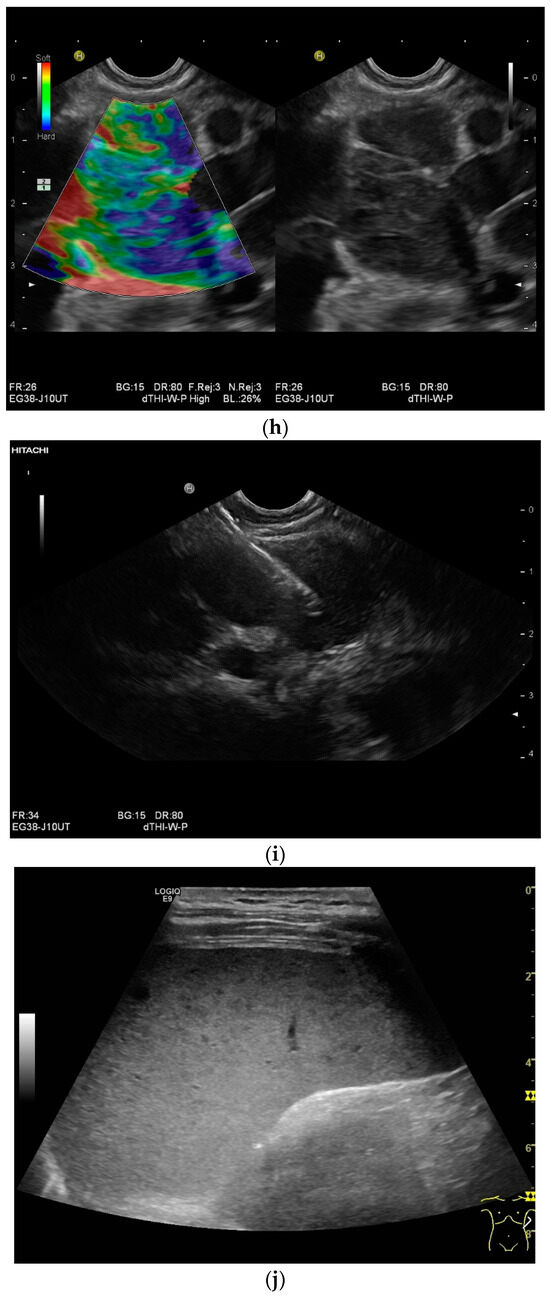

Figure 3.

Sonographic and CEUS features of hepatic tuberculosis. Subcapsular liver lesion (a); subcapsular liver lesions (white arrow) and hypoechoic lesion on the capsule (green arrow) using a linear transducer of 12 MHz (b). Caseous necrosis, histologically proven. Hypoechoic lesion with hyperechoic rim using B-mode ultrasound (right side of image). The lesion is hyperenhanced in the arterial phase at the edge of the CEUS; the center is nonenhanced with the exception of some enhanced septa (c). In the portal venous phase, the peripheral areas are hypoenhanced (d). Multiple small, smoothly bordered, non-cystic hypoechoic lesions in the liver, with no evidence of macrovessels when using Color Doppler Imaging (e). CEUS shows mild peripheral enhancement around the lesions. The lesions are without enhancement in the arterial phase (f), portal venous phase (g), and late phase (h).

Abscesses can develop from the caseous necrosis, but are rare [58]. The formation of a multiseptated liver abscess with numerous septa has also been described in a case study [60] [Figure 3c–g].

Ultrasound presents hypoechoic or isoechoic liver lesions [56]. Hyperechoic lesions are rarely described (although, these can be found in hepatitis B infections and hepatitis C-related liver cirrhosis; however, histologically confirmed cases have categorized these as tuberculoma related, and not as regenerative nodule or hepatocellular carcinoma (HCC)) [59,61]. Depending on the stage of the disease, the inflammatory lesions are homogeneously hyperenhanced via CEUS. Most lesions develop a washout in the portal venous phase. Melting abscesses show a hyperenhanced rim with either a hypoenhanced or nonenhanced center or a heterogeneous enhancement [62,63] [Figure 3c,d]. Vascular complications, such as portal vein thrombosis, have been caustically described and found to be in connection with hepatitis B [54,64].